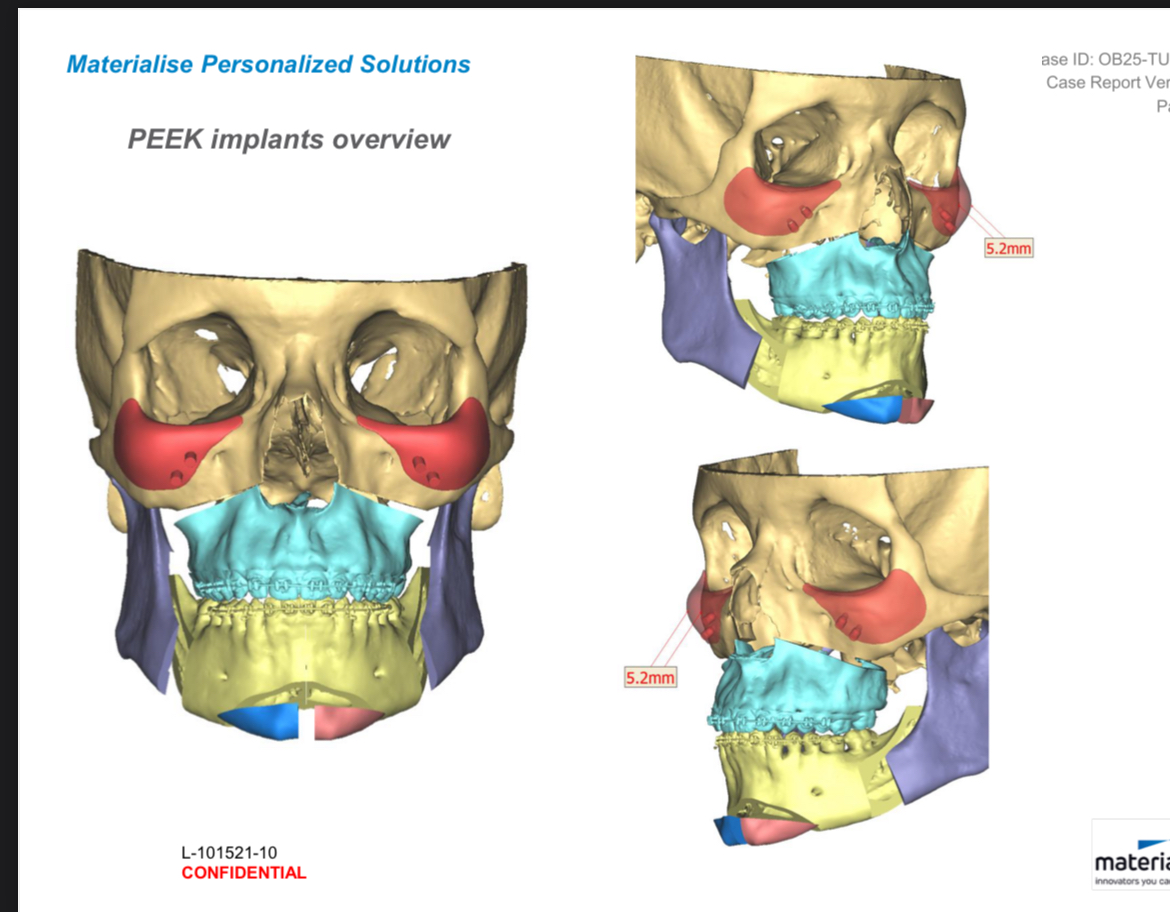

16mm genio-only projection with jawline implants. Clearly a trimax case, but for some bizarre reason, Ramieri chose to only do a genio instead. Note the deep mentolabial fold and the bunching around the submental from the transition between the chin and the rest of the mandible.

Case #2

Chin reduction and rotation to address asymmetry.

Look at the transition between the chin and the mandible; clearly a step-off. Is this because of chin shaving/reduction having the opposite of a tightening effect, or just simply poor technique on Ramieri's part?

Genio is supposed to be a relatively simple surgery, and hard to mess up. Is it really just poorly planned cuts or something else about the technique? Or is the step-off exaggerated in these after photos because of soft tissue swelling? Is the problem case-specific, or is Ramieri generally bad at genioplasties? I don't think it's fair to judge based on 2 cases and a few supposed forum anecdotes, but it doesn't set a good precedent for sure.